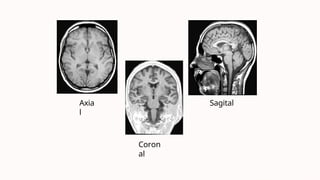

Planos de Corte em RM

Axial

O plano axial é

perpendicular à coluna

vertebral, como fatias

horizontais do corpo. É

usado para visualizar o

cérebro, a medula espinhal,

o abdome e outras

estruturas.

Sagital

O plano sagital divide o

corpo em direita e

esquerda, como fatias

verticais. É usado para

visualizar o cérebro, a

medula espinhal, o crânio e

a coluna vertebral.

Coronal

O plano coronal divide o corpo em anterior e posterior, como

fatias frontais. É usado para visualizar o cérebro, o rosto, o

peito e o abdômen.

Cortes Axial, Sagital e Coronal:

Abrangendo a Anatomia em

Diferentes Planos

1 Corte Axial

Corte perpendicular ao eixo Z,

mostrando a anatomia em um

plano horizontal, paralelo ao

plano cranial e podal.

2 Corte Sagital

Corte perpendicular ao eixo Y,

plano vertical, paralelo aos

planos laterais, dividindo o

corpo em metades direita e

esquerda.

3 Corte Coronal

Corte perpendicular ao eixo X, mostrando a anatomia em um plano

vertical, paralelo aos planos ventral e dorsal, separando os planos

ventral e dorsal.